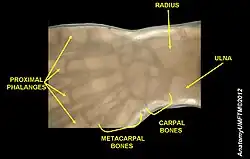

In human anatomy, the metacarpal bones or metacarpus, also known as the "palm bones", are the appendicular bones that form the intermediate part of the hand between the phalanges (fingers) and the carpal bones (wrist bones), which articulate with the forearm. The metacarpal bones are homologous to the metatarsal bones in the foot.

Each metacarpal bone consists of a body or shaft, and two extremities; the head at the distal or digital end (near the fingers), and the base at the proximal or carpal end (close to the wrist).

Base

The base (basis) or carpal extremity is of a cuboidal form, and broader behind than in front. It articulates with the carpal bones and with the adjoining metacarpal bones while its dorsal and volar surfaces are rough, for the attachment of ligaments.[2]

Head

The head (caput) or digital extremity presents an oblong surface markedly convex from before backward, less so transversely, and flattened from side to side; it articulates with the proximal phalanx. It is broader, and extends farther upward, on the volar than on the dorsal aspect, and is longer in the antero-posterior than in the transverse diameter. On either side of the head is a tubercle for the attachment of the collateral ligament of the metacarpophalangeal joint.